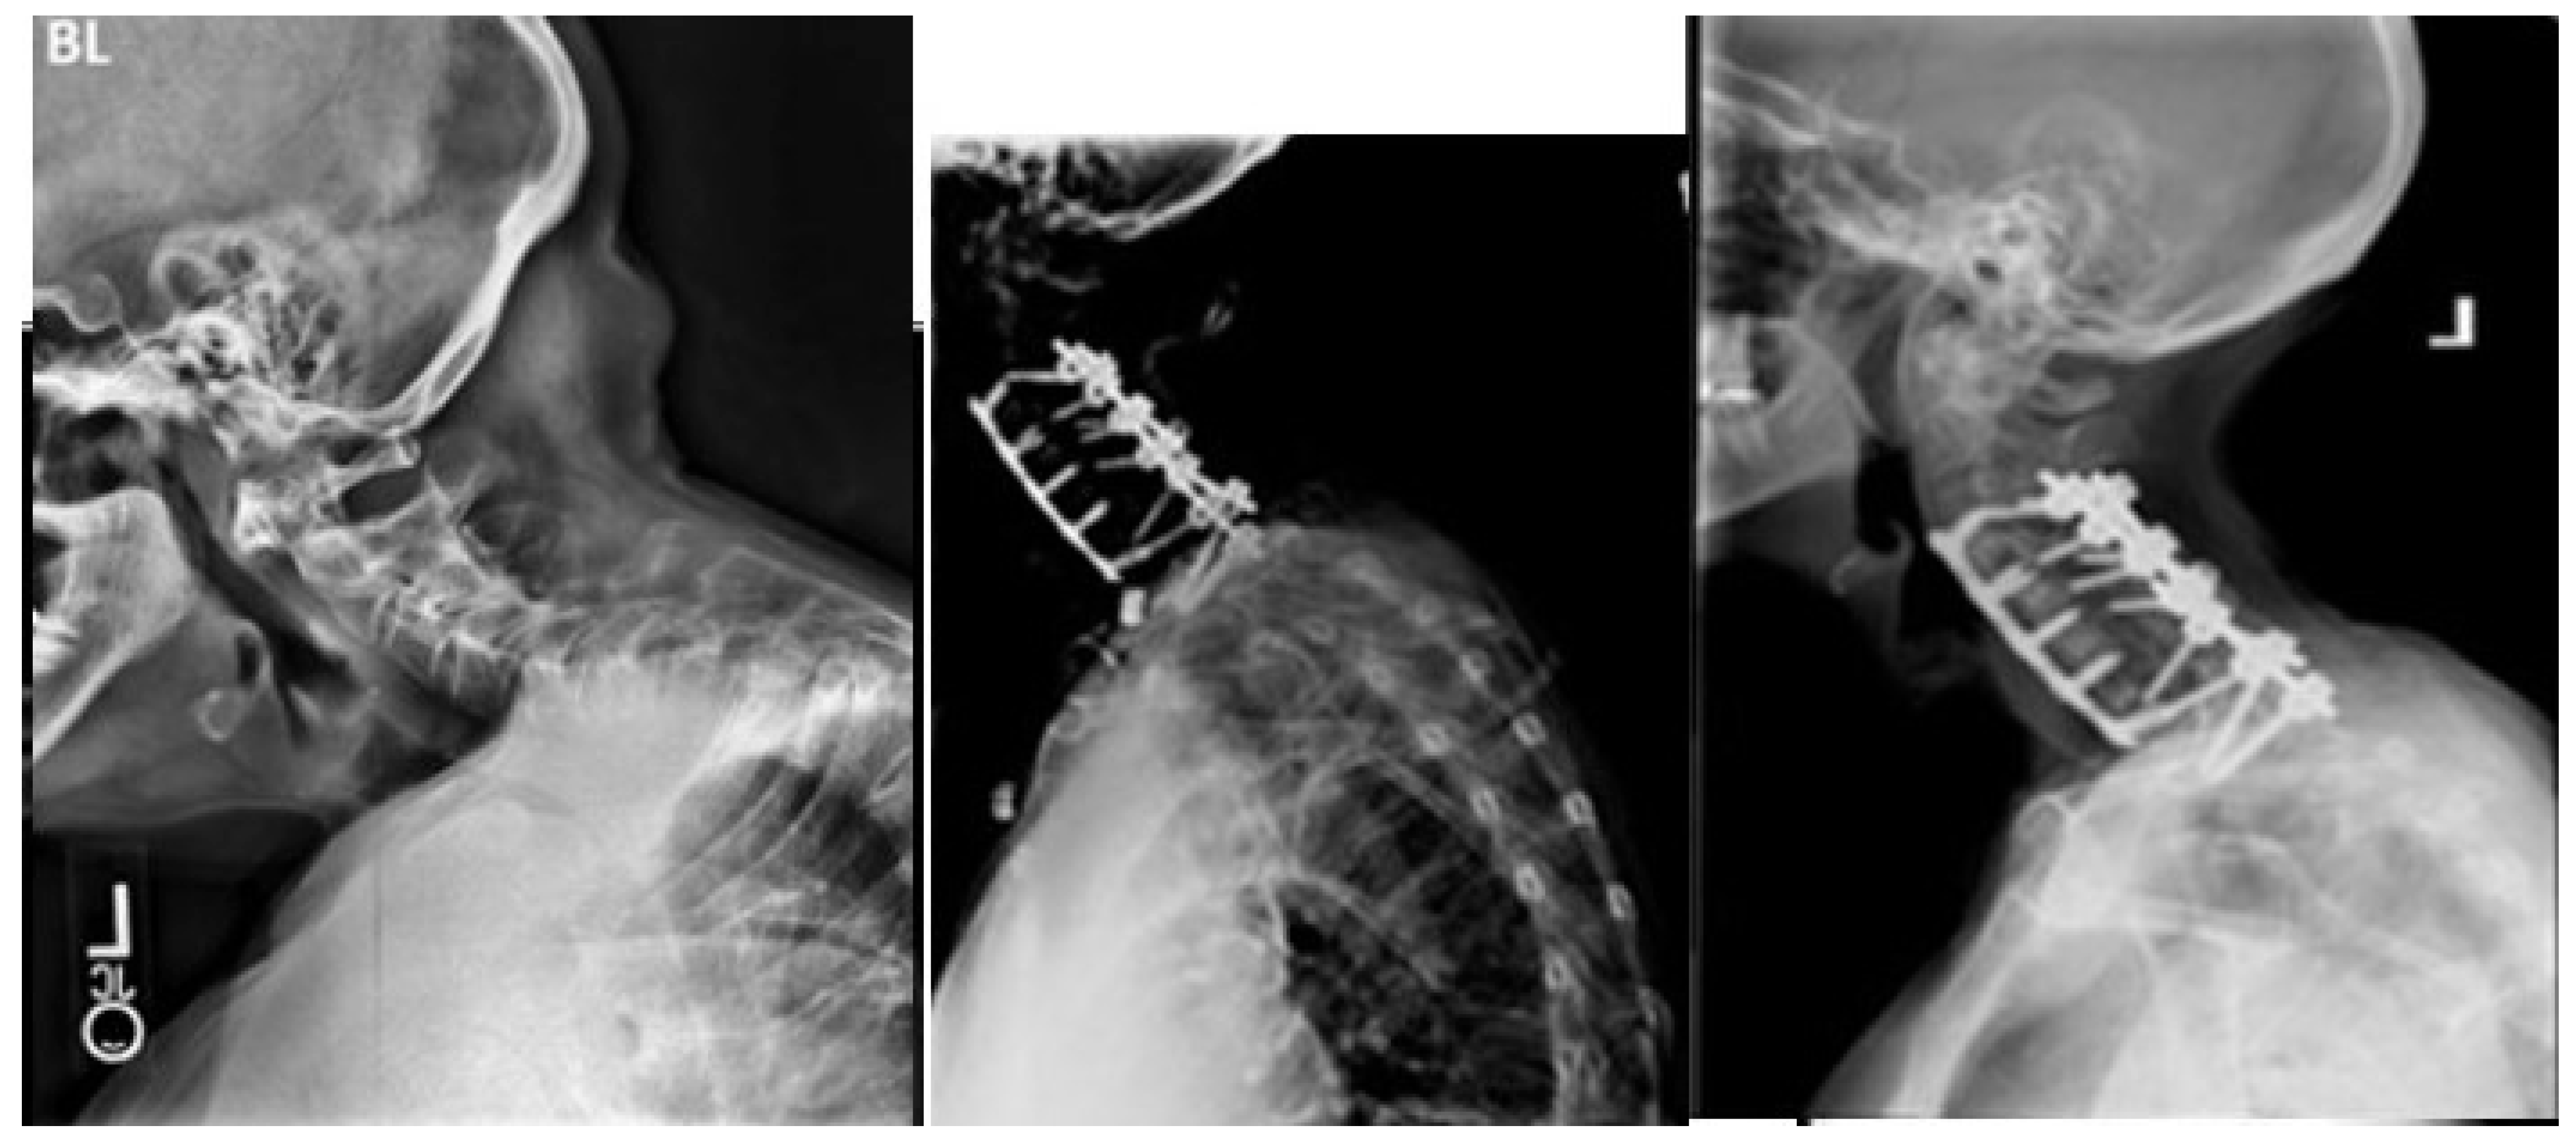

2. Methods

3.3. Postoperative Distal Junctional Kyphosis